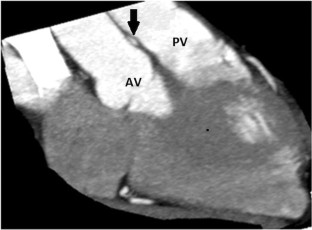

Fig. 1

Fig. 2

Fig. 3

Fig. 4

15. Angelini P, Flamm SD. Newer concepts for imaging anomalous aortic origin of the coronary arteries in adults. Catheter Cardiovasc Interv. 2007;69:942–54.

16. Cheong BY, Angelini P. Magnetic resonance imaging of the coronary arteries. In: Willerson JT, Holmes DR, editors. Coron Artery Dis. London: Springer-Verlag; 2007. p. 283–338.